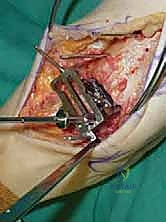

3. إزالة النتوءات العظمية وتحضير المفصل (Debridement)

بمجرد كشف المفصل، يقوم الجراح بإزالة الغشاء الزلالي الملتهب والزوائد العظمية (Osteophytes) التي تعيق الحركة. هذه الخطوة ضرورية لاستعادة المعالم التشريحية الطبيعية قبل إجراء القطع العظمي.

4. وضع أدلة القطع (Jig Placement and Alignment)

تعتمد دقة الجراحة على المحاذاة الصحيحة. يتم استخدام أجهزة توجيه متطورة (Jigs) تثبت على عظمة الساق باستخدام دبابيس معدنية. يتم التحقق من صحة الزوايا والمحاور باستخدام جهاز الأشعة السينية المباشر داخل غرفة العمليات (C-arm Fluoroscopy). يضمن الدكتور هطيف أن يكون القطع موازياً للأرض تماماً عند وقوف المريض.

5. القطع العظمي الظنبوبي (Tibial Bone Cut)

باستخدام منشار جراحي دقيق التذبذب، يتم إزالة شريحة رقيقة جداً (بضعة مليمترات) من السطح السفلي التالف لعظمة الظنبوب. يتم القطع بحذر شديد لتجنب إصابة الأوتار الخلفية أو الأوعية الدموية.